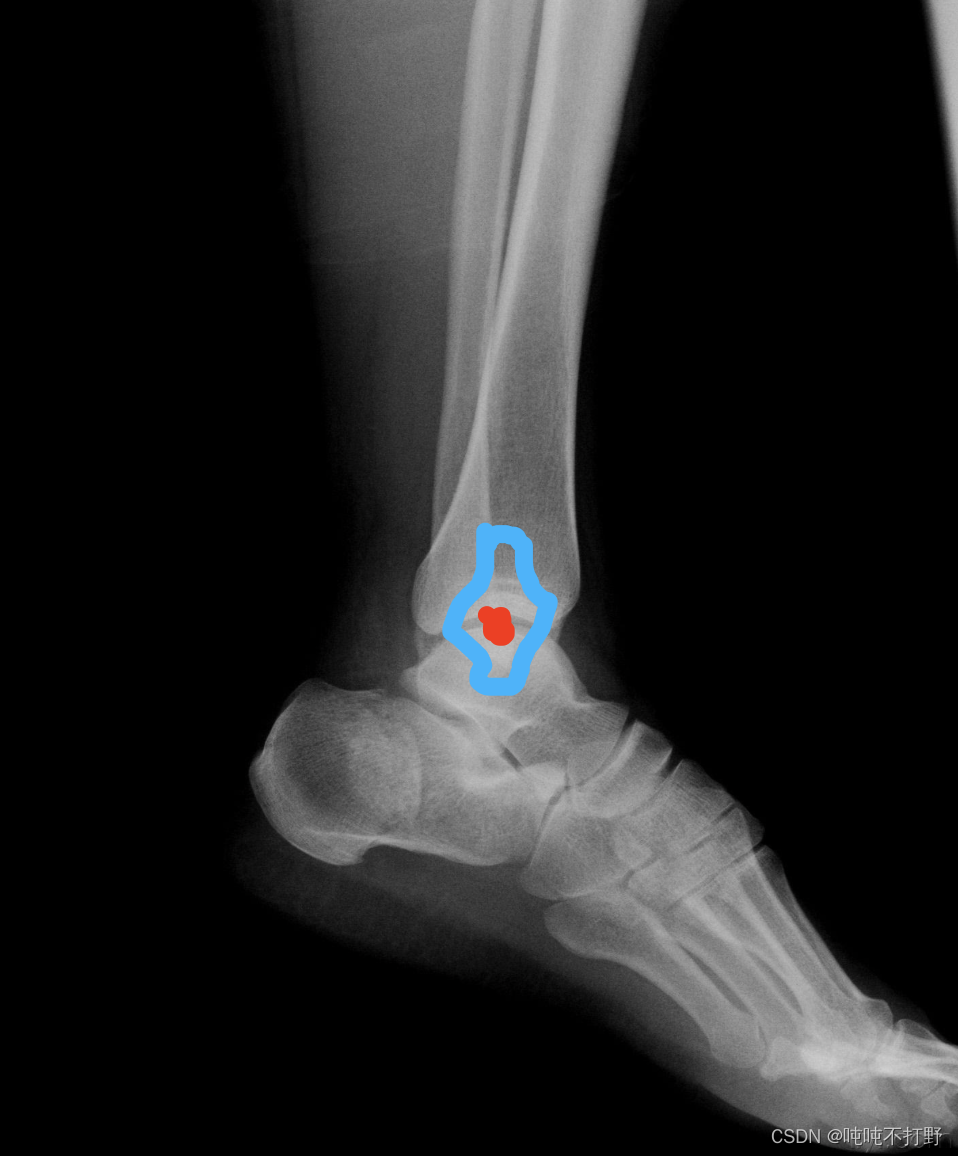

- 但是实际上,人体的关节有不同的形状如下图:踝关节,红色是关键点,蓝色围成的区域就是分布,不是个圆形,不是只靠一个方向的距离就可以衡量误差的(每个方向距离引起的误差在损失函数中权重应该是不同的):